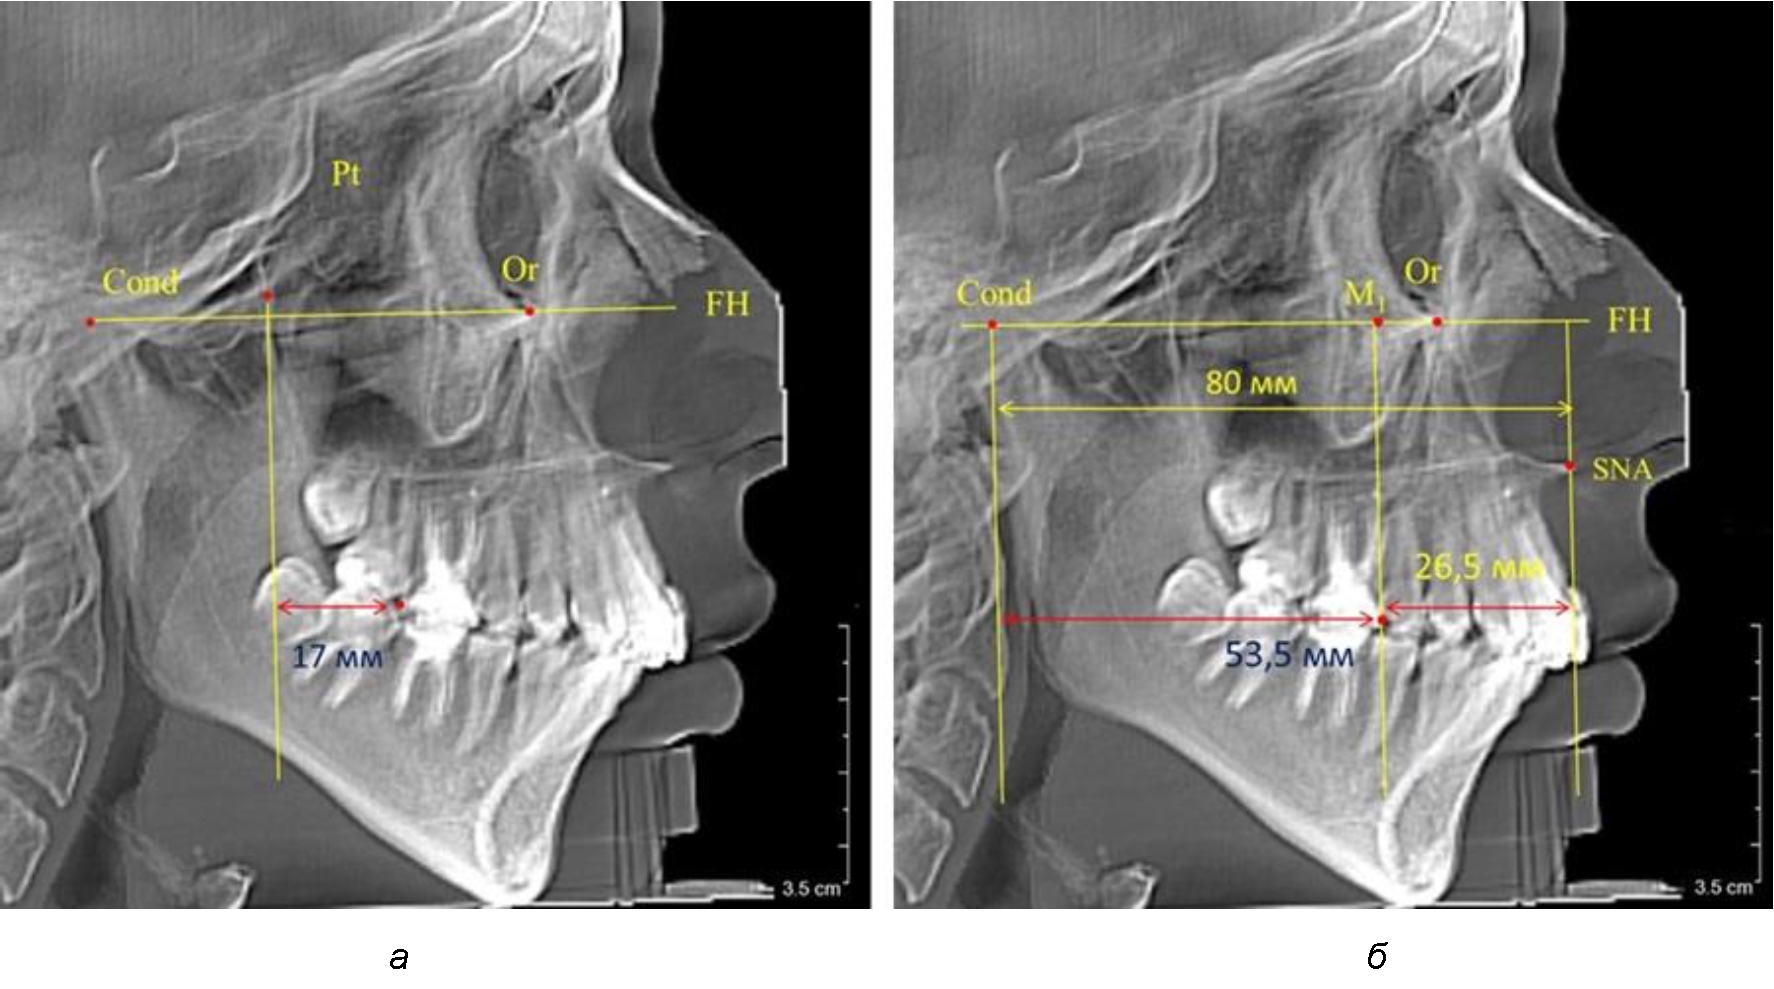

Рис. 2. Особенности положения первых моляров по R. E. McDonald (а) и по предложенному методу (б) при уменьшенном молярно-крыловидном расстоянии

Так, при расстоянии от крыловидной вертикальной плоскости PTV до дистальной поверхности верхнего первого постоянного моляра в 13 мм сагиттальный размер гнатического отдела был 82 мм. При этом отношение кондилярно-спинального расстояния к кондилярно-молярному размеру (54,5) было близким к коэффициенту 1,5, что представлено на рис. 2.

В то же время при увеличенном расстоянии от крыловидной вертикальной плоскости PTV до дистальной поверхности верхнего первого постоянного моляра, равное 23 мм, сагиттальный размер гнатического отдела составил 92 мм. При этом отношение кондилярно-спинального расстояния к кондилярно-молярному размеру (30,5), так же, как и при малых размерах, было близким к коэффициенту 1,5, что представлено на рис. 3.

Рис. 3. Особенности положения первых моляров по R. E. McDonald (а) и по предложенному методу (б) при увеличенном молярно-крыловидном расстоянии